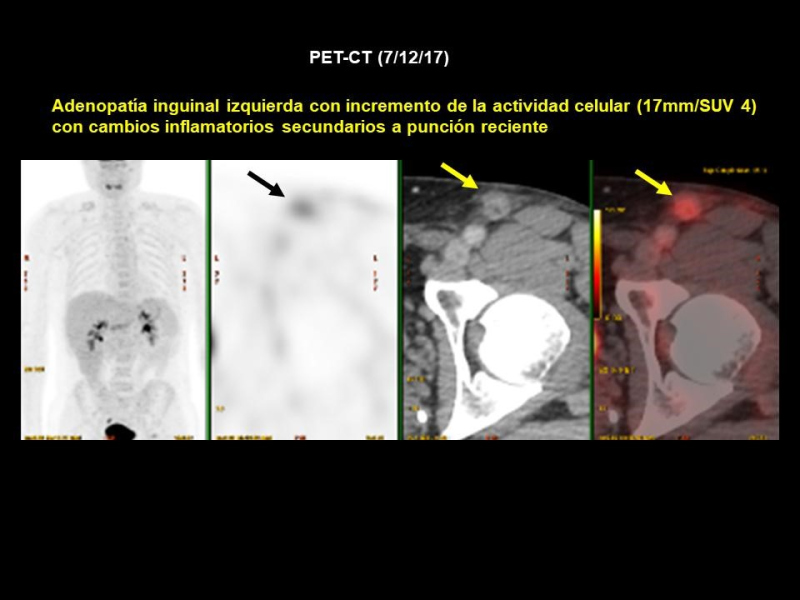

Se realiza PET-CT (7/12/17) previo a resección de adenopatía inguinal izquierda (Figs. 3 y 4), hallándose lesión focal de 14 mm con incremento de actividad metabólica (SUV 8,3) situada a nivel del músculo glúteo mayor izquierdo sugestivo de implante secundario, sin traducción morfológica en CT. Además, adenopatía inguinal izquierda con incremento de la actividad metabólica (17mm/SUV 4) compatible con posibles cambios inflamatorios secundarios a punción reciente. Una nueva ecografía muestra lesión nodular en el espesor del músculo glúteo mayor, en relación con depósito secundario, de fácil acceso y susceptible de marcaje por ROLL (Fig. 5). También se encuentran dos adenopatías inguinales izquierdas, con criterios de posible secundarismo ganglionar.